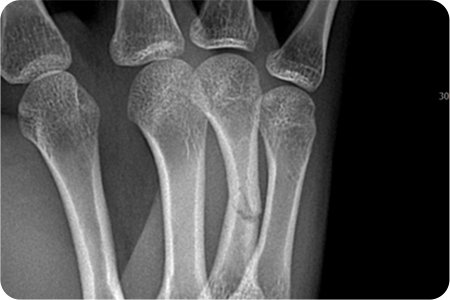

손 뼈 골절 수술

손은 작은 뼈들이 정교하게 연결되어 있어

골절 시 기능 손상이 크기 때문에,

정확한 정복과 고정이 중요합니다.